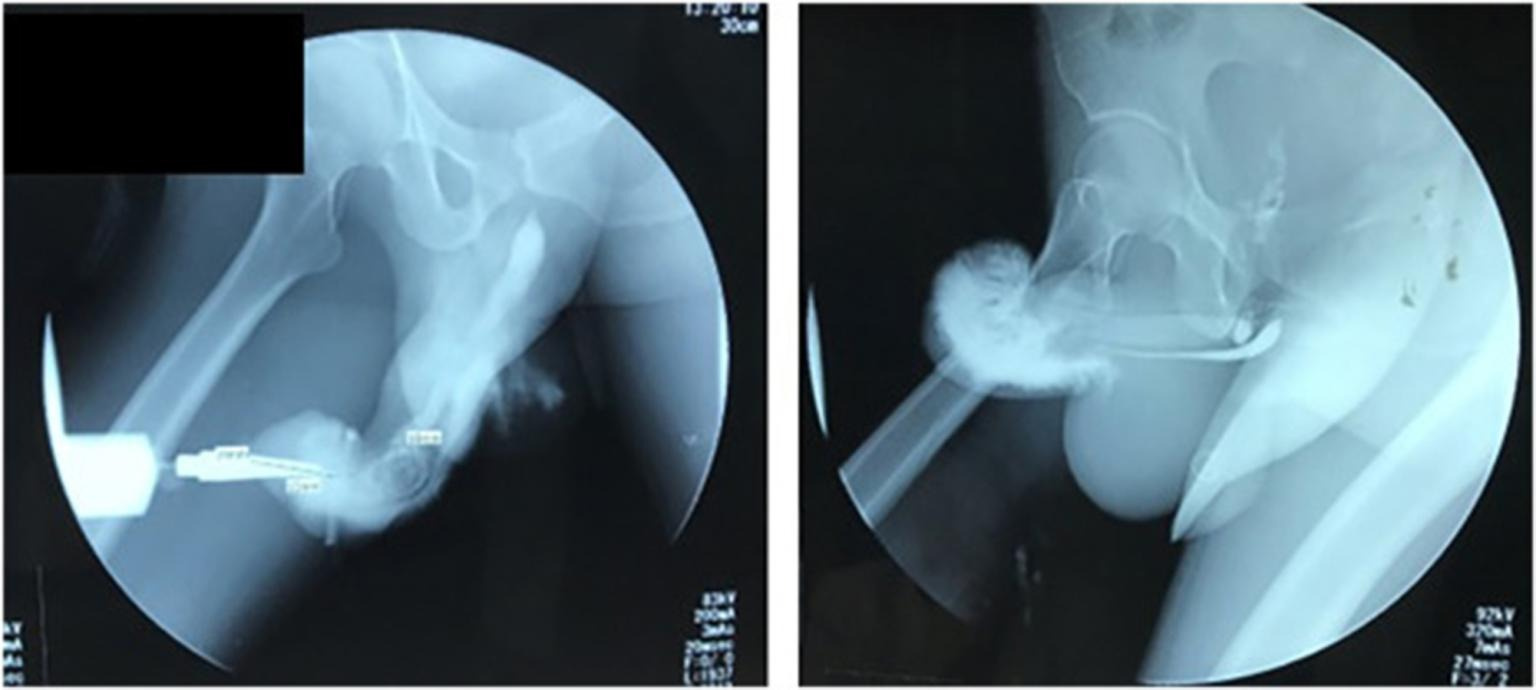

Мужчине из Индонезии пришлось перенести экстренную операцию после того, как он сломал пенис из-за рискованной позы во время секса. Исследование случившегося опубликовали в журнале Urology Case Reports. Несчастный случай произошел, когда неназванный 37-летний мужчина решил попробовать со своей возлюбленной положение «обратной наездницы» (“reverse cowgirl”): женщина находилась сверху и спиной к своему мужчине.

Как ломается пенис